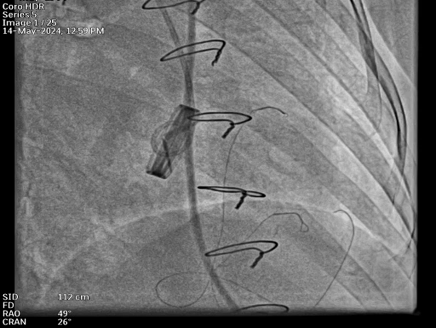

Bedside ECHO showed Prosthetic Valve Thrombosis and Fluoroscopy confirmed that both the leaflets were stuck

Fluoroscopy Revealed Stuck Prosthetic leaflets. She was planned for emergency percutaneous management in view of her present clinical and lab fincdings

Bilateral Radial and Femoral artery access taken along with Right Femoral vein under Ultrasound guidanceCarotid filter was placed in Right carotid artery through Right femoral arteryTwo Peripheral balloons were kept in left common carotid and left subclavian through left femoral and radial artery routeTranseptal puncture through right femoral vein was done and was later exchanged with 8.5fr deflectable Agilis sheathThrough Agilis sheath valve orifices was crossed with 0.032 Terumo wireUpper Orifice was dilated with 12x140mm peripheral balloonCentral Orifice was dilated with 5x60mm peripheral balloonLower Orifice was dilated with 10x140mm peripheral balloonPost Procedure Good movement of both leaflets , still upper leaflet movement was not satisfactory.6fr Decapolar mapping catheter was used for pecking the upper leaflet and later again it was dilated with 12x140mm peripheral balloon.Movement of both leaflets were good